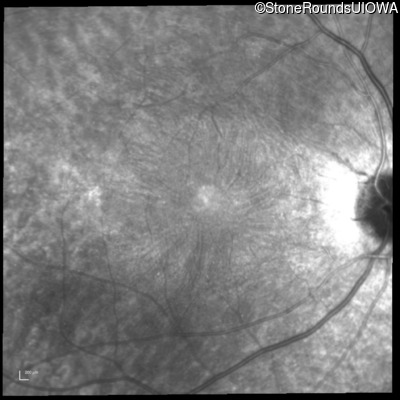

Infrared Fundus Photograph - Right -

20/20 -1

Infrared Fundus Photograph - Left -

20/20 -2